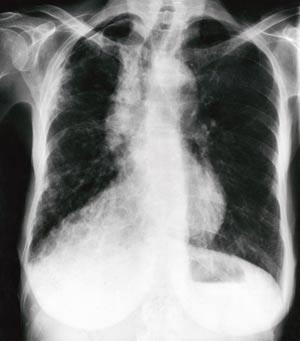

Pasienten. En 63 år gammel hjemmeværende husmor var synssvekket og hadde nedsatt hørsel. Pasienten røykte fra hun var 43 til 60 år. På grunn av residiverende urinveisinfeksjoner hadde hun flere ganger brukt nitrofurantoin 100 mg daglig. Hun ble første gang innlagt i sykehus primo januar 1996 på grunn av muskel- og leddsmerter, hodepine og forkjølelsessymptomer, et sykdomsbilde som ble journalført som influensa. Dessuten hadde hun tørrhoste, åndenød, hjertebank og inspiratoriske knatrelyder over begge lunger fra basis til topp. Arterielle blodgasser viste PaCO₂ 4,5 kPa, PaO2 8,3 kPa og O₂-metning 92 %. Røntgenbildet av thorax var normalt. Blodprøver viste leukocytter 10,6 10⁹/l, SR 55 mm/t, IgG 27 mg/l (normalt 7 – 15 mg/l) og ANA 40 enh/l (normalt < 32 enh/l). Spirometri viste et restriktivt mønster med FVC 1,75 l (67 % av forventet) (8), FEV1 1,51 l (69 %) og FEV₁/FVC 0,87. Tilstanden ble oppfattet som «furadantinlunge». Nitrofurantoin ble seponert og pasienten utskrevet med avtale om henvisning til sykehusets lungepoliklinikk ved nye symptomer. Ultimo februar 1997 kom hun til poliklinikken på grunn av progredierende åndenød. Røntgen thorax viste flekkvise fortetninger i høyre midt- og overlapp, men venstre lunge var upåfallende. FVC var 1,20 l (47 %), FEV1 1,08 l (50 %). FEV₁/FVC 0,89. Faren med å bruke nitrofurantoin ble på nytt poengtert. Computertomografi med høy oppløsning (HR-CT) viste diffuse fortetninger mest på høyre side forenlig med fibroserende alveolitt. I januar 1998 ble hun igjen henvist fordi hun var blitt tyngre i pusten, hadde taledyspné, takypné, tørrhoste, hjertebank, leppecyanose og et vekttap på 4 – 6 kg. Røntgen thorax viste økende lungefibrose, mest uttalt i basale og midtre lungefelt på høyre side og en 2 centimeters pneumothoraxkappe over høyre lungetopp (fig 1). Spirometri viste betydelig forverring siden januar 1996 med FVC 0,85 l (33 %). FEV₁ 0,78 l (37 %) FEV₁/FVC 0,91. Blodgasser viste PaCO2 5,3 kPa og PaO2 7,8 kPa. Lungebiopsi tatt ved torakoskopi var forenlig med hypersensitiv pneumonitt/granulomatøs alveolitt. Ektefellen ble oppfordret til å møte ved utskrivningssamtalen på grunn av pasientens tunghørthet. Han kom til legekonsultasjonen med følgende skriftlige spørsmål: «Hvordan oppstår sykdommen og hvordan er utsiktene? Er det ting eller forhold vi bør være oppmerksomme på? Kan bomiljøet ha vært av betydning og/eller kan det være av betydning fremover? Vi er glad i dyr og fugler og pasienten er i daglig kontakt med to hunder, to katter, 21 finker, 12 undulater, fire parakitter, fire dvergpapegøyer og to duer.» Han opplyste at ekteparet hadde hatt stuefugler i mer enn ti år. Undersøkelse på presipitater i serum viste kraftig positive immunpresipitater mot samtlige fugleantigener (fig 2). Det ble startet med prednisolon 40 mg dgl, dosen ble trappet ned og seponert etter åtte måneder. Pasienten var nær knyttet til sine fugler og først etter flere legekonsultasjoner lyktes det å få pasienten til å kvitte seg med fuglene. Lungefunksjon i oktober 1998 viste fortsatt restriksjon med FVC 1,26 l (50 %), FEV1 0,99 l (47 %), FEV₁/FVC 0,78. Arterielle blodgasser viste PaO₂ 9,3 kPa og PaCO2 5,1kPa. I mai 2003 ble pasienten innlagt med akutt åndenødsforverring, feber og PaO2 5,7 kPa. Ved spiral-CT var det en sentral embolus i lungearterie. Venografi viste dyp venetrombose i høyre underekstremitet. Senere polikliniske konsultasjoner frem til 2003 har vist betydelig restriktiv ventilasjonsinnskrenkning med redusert gassutveksling.

Pasienter med det akutte sykdomsbildet har i opptil 70 % av tilfellene normale funn på røntgen thorax, men noen utvikler mikronodulære lungefortetninger helst i midt- og underlapp (1). HR-CT er en mer sensitiv bildediagnostikk enn vanlig røntgen thorax, og lungeaffeksjon påvises tidligere (2). I en tidlig fase av sykdommen er det mulig å forhindre en varig irreversibel lungeskade ved å påvise eksponeringen og å fjerne den. Vår pasients bruk av nitrofurantoin gjorde at vi primært ikke tenkte på andre årsaker. Etter at sykdommen hadde gått inn i en subakutt/kronisk fase, oppstod de interstitielle lungefortetningene i høyre midt- og overlapp. Kronisk eksogen allergisk alveolitt er røntgenologisk ofte asymmetrisk lokalisert i lungene (1).